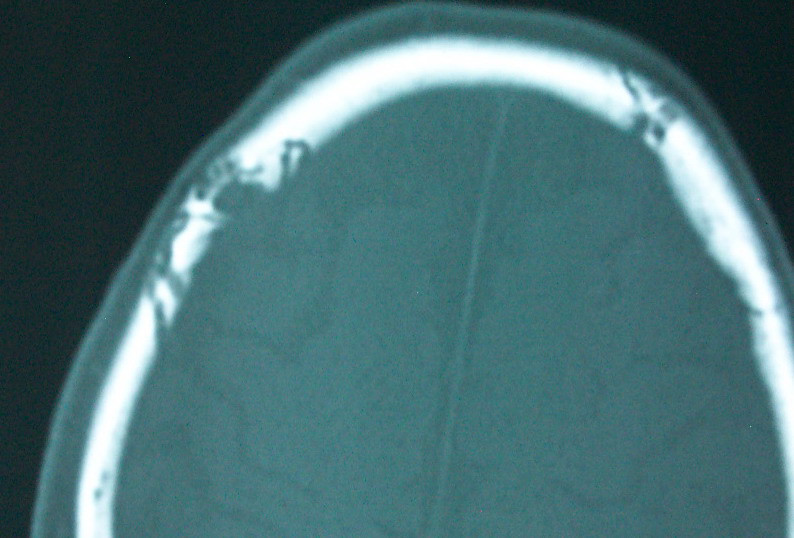

以下是引用余辉在2009-4-15 20:49:00的发言:[br]右侧病灶发生于冠状缝区,但额骨左侧鳞也有病灶,病灶区脑沟裂增宽(有脑萎缩征像,把这个征像放在颅骨病变一起考虑可能有点牵强),是否可能是板障血管畸形所致谢?抑或是嗜酸性肉芽肿或蛛网膜粒压迹那类东西?

以下是引用whzht在2009-4-15 20:57:00的发言:[br]1、额骨改变,考虑蛛网膜粒压迹;[br]2、脑萎缩。